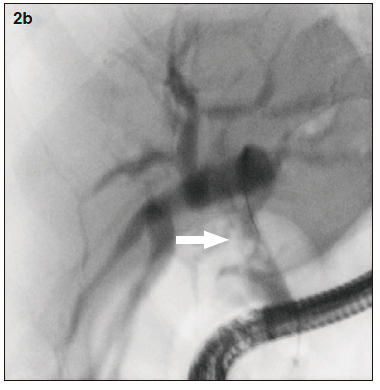

Figura 2b. Descenso de los litos luego de la tutorización del conducto hepático derecho

El estudio por colangioresonancia evidenció una variante anatómica biliar tipo 3 de la clasificación de Huang, ya que el conducto hepático posterior derecho drenaba en el conducto hepático izquierdo.1 Se observaron imágenes compatibles con litiasis intrahepática derecha y litiasis en el colédoco distal. La CPRE confirmó la presencia de la variante anatómica del patrón ductal hepático derecho y permitió realizar una canulación selectiva con posterior extracción de litos mediante balón y canastilla.2 El paciente tuvo una buena evolución clínica sin complicaciones.